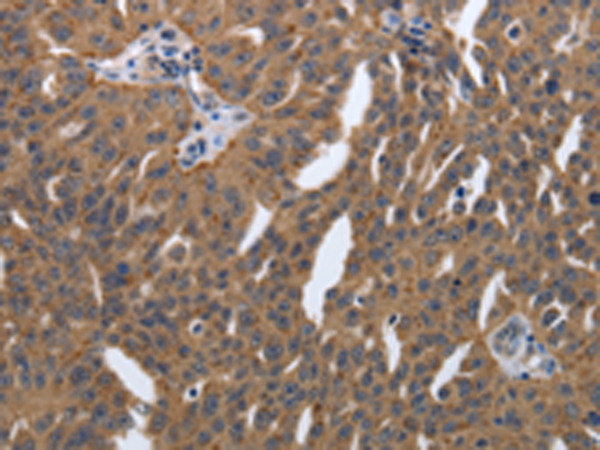

分类: 科研抗体货号: P11315别名: PDI, PDA2, PDIP, PDIR应用: IHC反应种属: Human